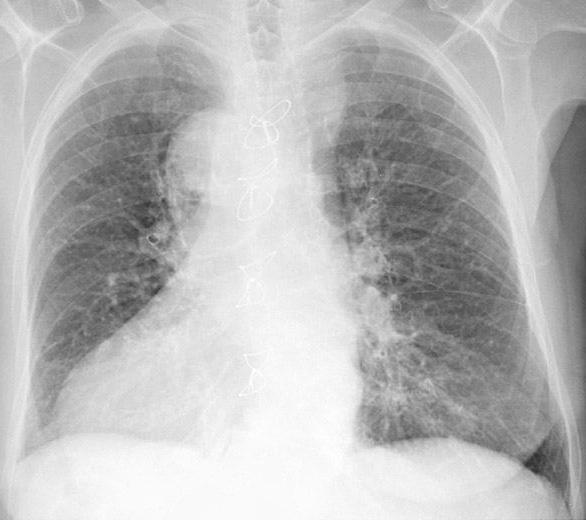

Посредством рентгена или ультразвукового исследования специалист сможет установить факт отечности, а также определить количество жидкости в пораженном органе. На этом этапе очень важно не только выявить жидкость и ее количество в легких, но и обозначить причины появления недуга. Слаженная и безотлагательная работа специалистов поможет правильно и в кратчайшие сроки назначить курс лечения, который впоследствии устранит причину отека легких и снизит кислородное голодание.

Определить скопление жидкости в легких очень просто, достаточно сделать рентгенографию грудной клетки. После подтверждения диагноза необходимо пройти ультразвуковое исследование, чтобы определить количество воды в легких.

- рентгенологическое исследование грудной клетки или флюорография;